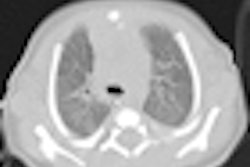

All of this is controlled by a Web-based graphical user interface that allows a user to perform both simple and advanced searches. Information that is retrieved is displayed in a ranked list that contains a small amount of report content and a key image thumbnail.

With increased use of RadMiner, the percentage of radiology reports that include key image references has increased, according to the authors. This is improving the number of search results with meaningful images.